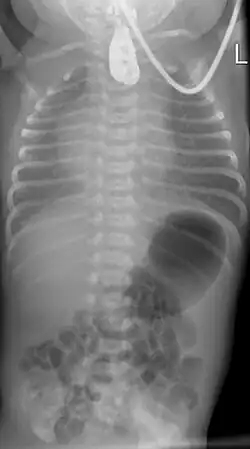

Zur Diagnosefindung wird die Speiseröhre sondiert. Ein federnder Stopp ist hinweisend. Eine Röntgenaufnahme des Brustkorbes zeigt die Luftfüllung des oberen Blindsackes (sog. Medaillonzeichen), und gegebenenfalls eine Luftfüllung des Darmes als Hinweis auf eine untere Fistel. Nur in Ausnahmefällen wird zusätzlich wasserlösliches Kontrastmittel gegeben.